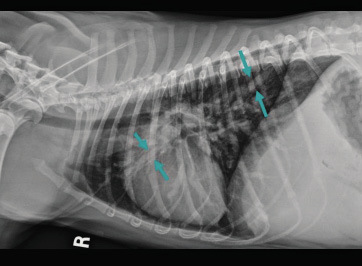

Istnieje wiele schorzeń, które mogą powodować symptomy podobne do zapalenia płuc, takie jak infekcje pasożytnicze, choroby serca czy nowotwory płuc. Dlatego w celu zdiagnozowania zapalenia płuc u psa przeprowadzany jest dokładny badanie kliniczne, które często uzupełniane jest rentgenem i analizą krwi, co może dostarczyć dodatkowych informacji dotyczących przyczyny zapalenia płuc. Rzadko infekcje bakteryjne są pierwotnym powodem, zazwyczaj są to wtórne* infekcje bakteryjne*, które rozwijają się w wyniku obniżenia odporności dróg oddechowych i płuc przez inne czynniki, takie jak infekcja wirusowa lub grzybicza.